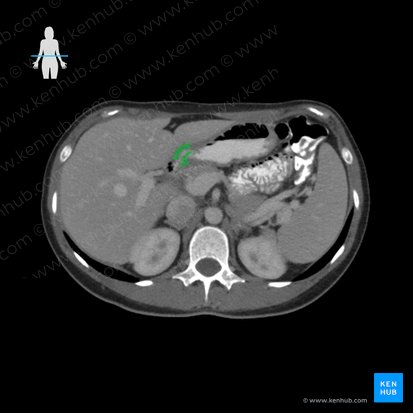

The pylorus is the funnel-shaped distal-most segment of the four anatomical regions of the stomach, with the others being the cardia, fundus and body of the stomach. It extends from the distal end of the body of the stomach at the angular notch to the gastroduodenal junction and is divided into two segments: the pyloric antrum and pyloric canal. The pyloric antrum is the wider and more proximal of the two regions connecting to the body of the stomach, with the narrower pyloric canal being the distal portion connecting to the duodenum. At the end of the pyloric canal is the pyloric orifice, marking the junction between the stomach and duodenum. The pyloric orifice passes through the transpyloric plane, just to the right of the midline.

Surrounding the pyloric orifice is a thickened circular layer of smooth muscle known as the pyloric sphincter, controlling the opening and closing of the orifice. The pyloric sphincter therefore regulates the passing of food (chyme) from the pylorus of the stomach into the duodenum.